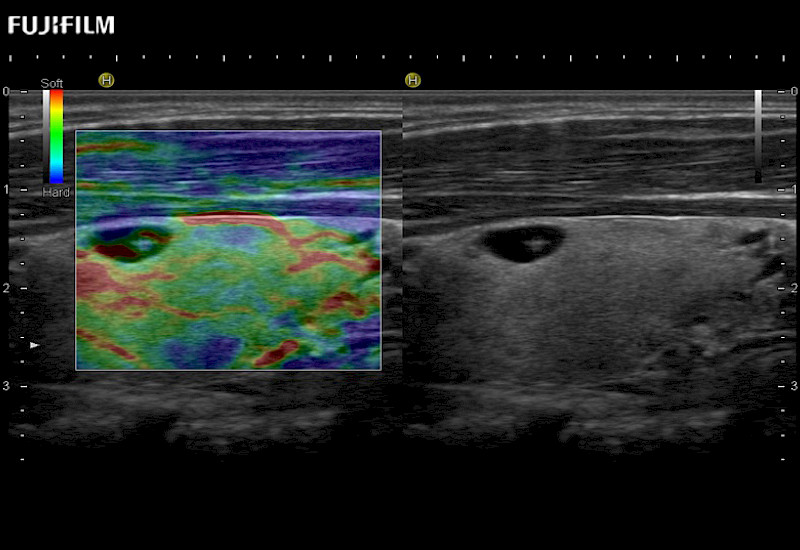

The ARIETTA 750 incorporates all of the proven technologies and functions that medical professionals have come to expect from Fujifilm Healthcare.

ARIETTA 750 is the definitive diagnostic ultrasound solution for any clinical setting - Private Office, Imaging Center, or Hospital. The ARIETTA platform provides the ultimate in clinical performance with its state-of-the-art features and large user-friendly display.

The ARIETTA 650 DI combines trusted Fujifilm Healthcare technologies and features tailored for surgical oncology.

Designed to meet the demands of surgeons, the ARIETTA 650 DI offers precise guidance. Its advanced capabilities and large, intuitive display offer accurate and efficient care in operating rooms and specialized surgical settings.